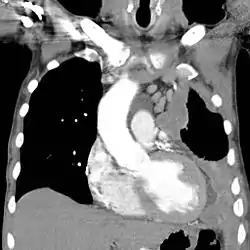

![]() ورم المتوسطة في الجانب الأيسر مع تضخم العقد المنصفية (تصوير مقطعي محوسب). ورم المتوسطة في الجانب الأيسر مع تضخم العقد المنصفية (تصوير مقطعي محوسب). | |